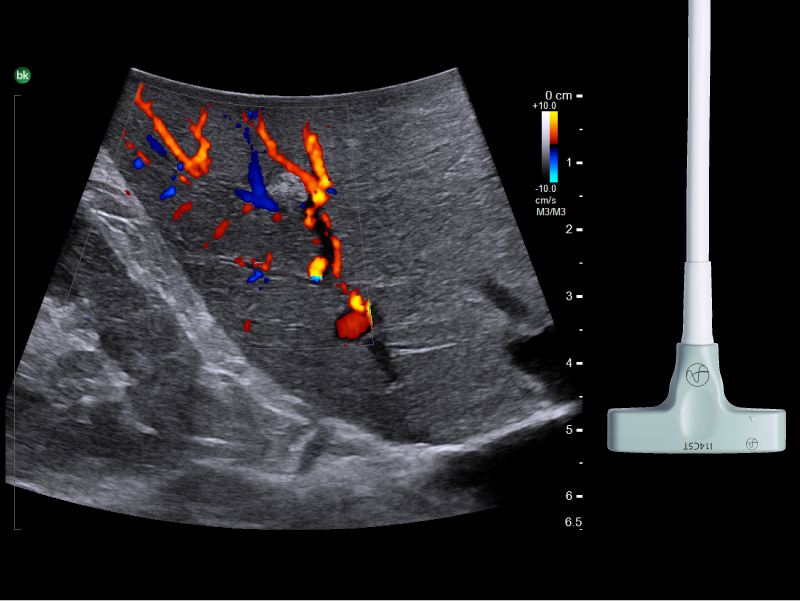

Pancreatic head mass, visualized with Biplane Transducer

Use of intraoperative ultrasound can influence

surgical decision-making in up to

of pancreatic resections5